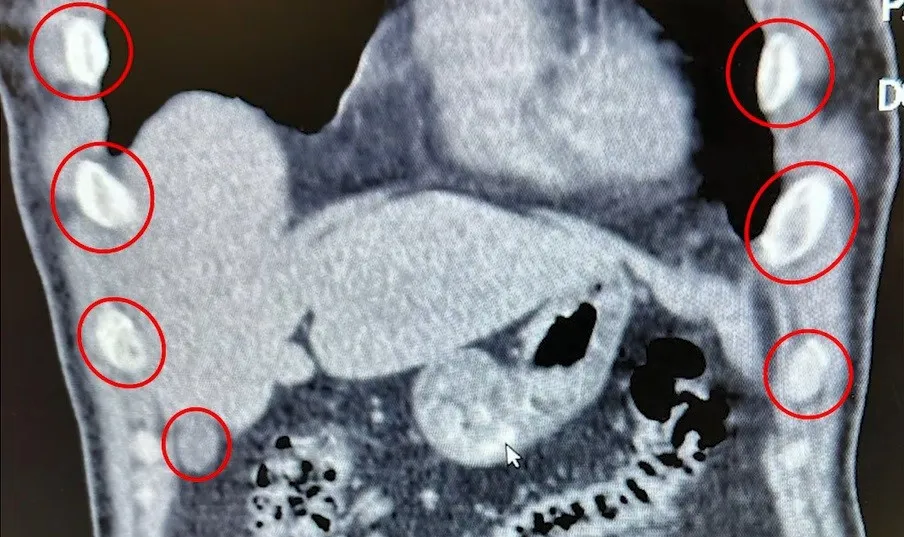

Şahıslar, kontrollerin yapılması amacıyla Tatvan Devlet Hastanesi’ne sevk edildi. Hastanede yapılan röntgen ve tomografi görüntülemelerinde şahısların mide ve bağırsaklarında çok sayıda yabancı cisim tespit edildi.

Gerçekleştirilen tıbbi müdahale sonucunda, zanlıların yutmuş olduğu 136 kapsül içerisinde toplam 1 kilo 48 gram Metamfetamin maddesi ele geçirildi.